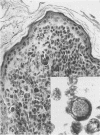

Melanocytes in melanocytic naevi and melanomas can display great variation. The presence of nuclear pseudoinclusions (NPI) is said to be useful in the histological and cytological differential diagnosis of malignant melanoma. The prevalence and characteristics of NPI in a series of 493 naevi and 50 melanomas are described. NPI were found in 31% of adult naevi, 30% of congenital naevi from children, 42% of Spitz naevi, 20% of dysplastic naevi, and 56% of melanomas. The presence of NPI is not a reliable criterion for differentiating melanoma from benign melanocytic lesions, although it is useful in distinguishing melanocytic from non-melanocytic tumours.